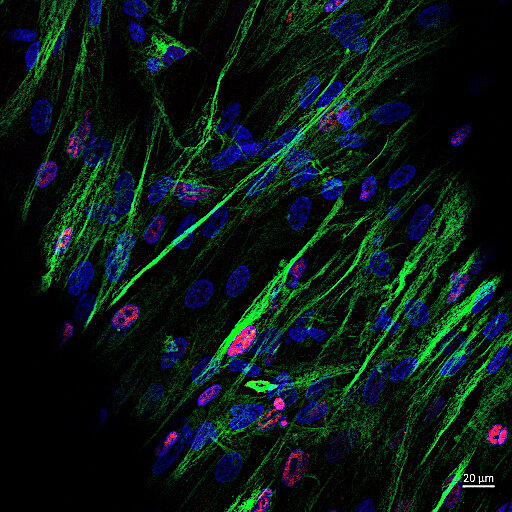

RealBrain® captures the complexity of the brain by differentiating neural stem cells in an advanced, chemically defined polymer matrix. The resultant 3D models contain a heterogeneous cell population with functional neural networks in a cell-secreted ECM. These models are fully compatible with 96 and 384-well plate formats, can be produced in just 3 weeks, and offer excellent reproducibility and optical clarity.

The hetergeneous cell population of neurons, astrocytes and glia demonstrates a range of neural functionality

Synaptic maturity: Functional synapses with pre- & post-synaptic markers

Responsiveness: Neurotransmitters including acetylcholine, serotonin, norepinephrine

Voltage gated channels: K+ and Na+ currents across a range of membrane potentials